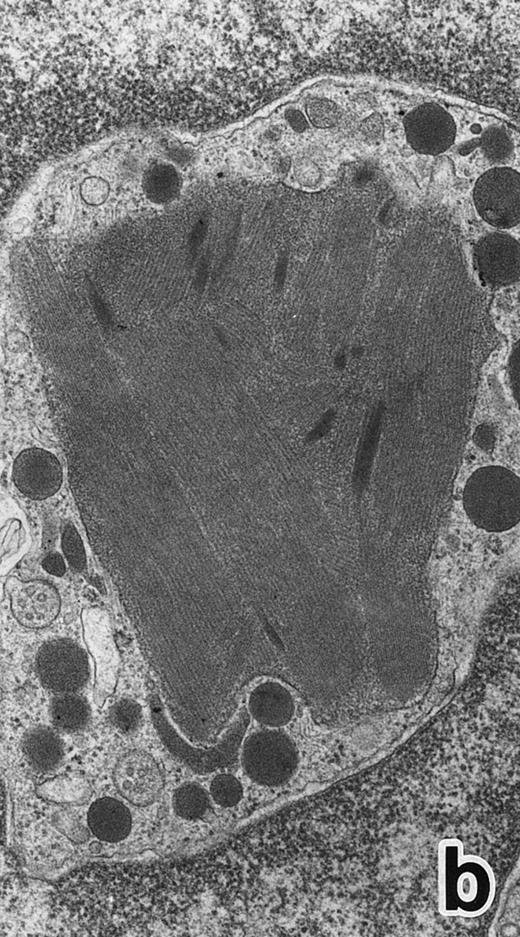

(a) A PMN in patient no. 1 that appeared in the bone marrow after 3 weeks of ATRA treatment. There are numerous granules in the cytoplasm, including spherical, elongated, and even dumbell-shaped granules, all of which are MPO-positive, ie, primary granules. A lipid droplet (L) is also present. (MPO-stained section, original magnification × 15,200.) (b) Higher magnification of a portion of the cytoplasm in (a). MPO-negative secondary granules are not seen. (MPO-stained section, original magnification × 30,900.)